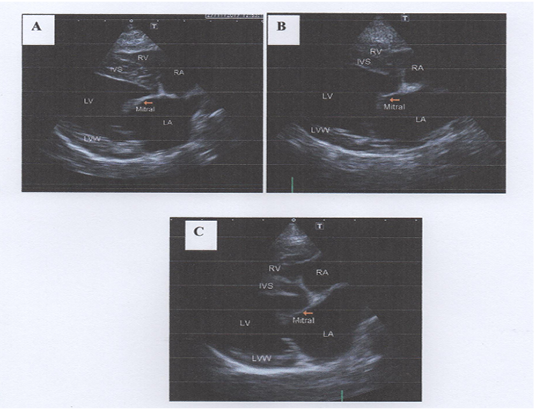

Thickened mitral valve at right parasternal long axis four-chamber view. 2-A: Mild thickening of mitral valve, 2-B: Moderate thickening of mitral valve and prolapse of the anterior leaflet, 2-C: Severe thickening of mitral valve and mitral valve prolapse (MVP) of the anterior leaflet towards left atrium.